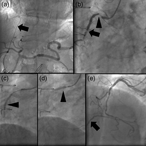

Severe pelvic fracture with profound hypotension: a case report and treatment algorithm

Chadwick J. Knight and others

Journal of Surgical Case Reports, Volume 2017, Issue 6, June 2017, rjx093, https://doi.org/10.1093/jscr/rjx093